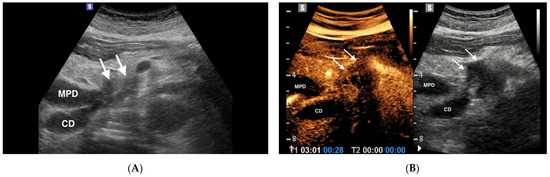

4.1.1. IPMN

4.1.2. MCNs